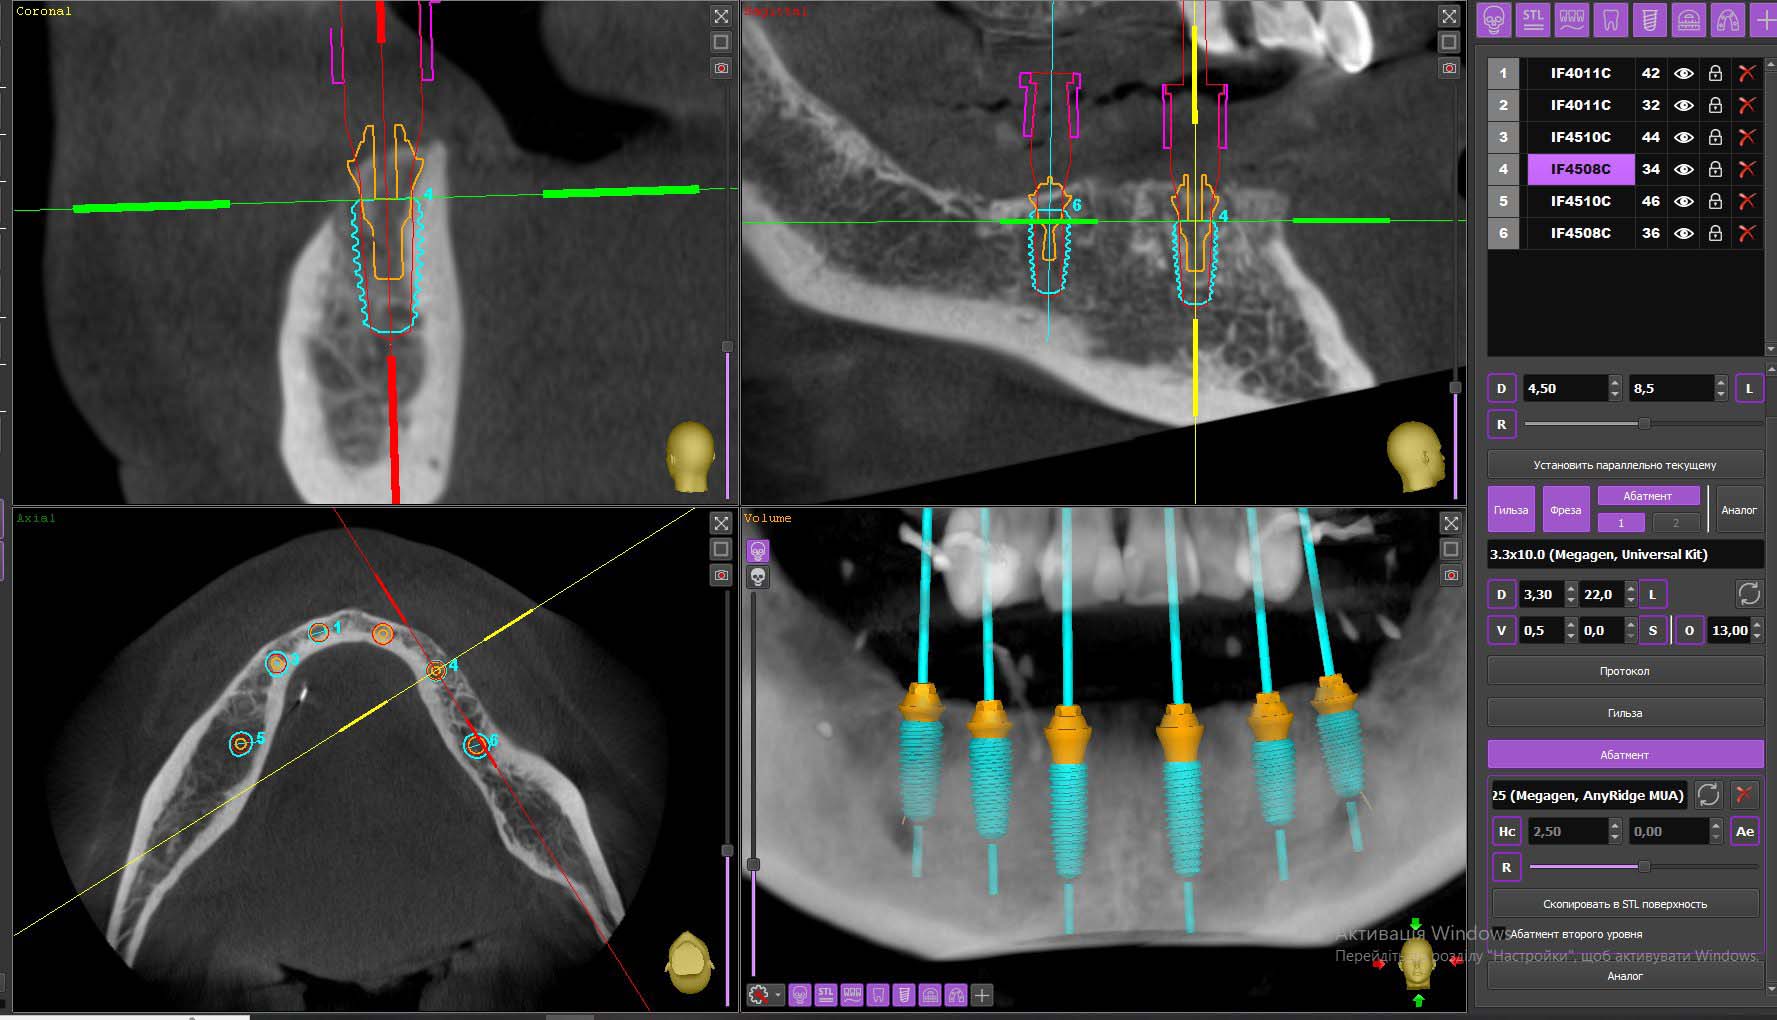

Діагностика

Комп'ютерна томографія дозволяє ретельно визначити:

• структуру та стан кістки;

• гайморові пазухи та їх місцезнаходження з точністю до міліметра;

• приховані патології.

Обов'язковий етап – діагностика скронево-щелепного суглоба. Це допомагає грамотно виготовити незнімний протез, щоб розподілити навантаження між суглобами та виправити патологію прикусу. За відсутності протипоказань до імплантації All-on-6 лікар готує план лікування.

На комп'ютерній програмі лікар готується до операції, щоб унеможливити ризик помилок. Хірург створює візуалізацію майбутньої щелепи та прототип конструкції. З точністю до міліметра він вибирає місця для встановлення імплантів. Наступний етап підготовки – санація ротової порожнини. Ретельним чищенням стоматолог видаляє наліт, камінь, а також лікує запалення.